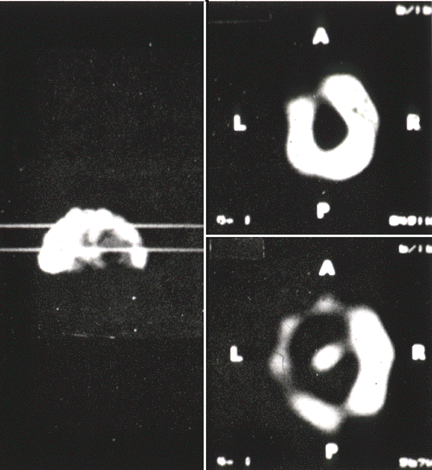

Todos esses progressos, aliados à adaptação dos algoritmos de reconstrução computadorizada axial, desenvolvidos para o tomógrafo de raios X, por Cormack e Hounsfield, levou a uma boa resolução de imagens nos equipamentos SPECT atuais. No entanto, a resolução e a eficiência da imagem, ainda são menores do que as obtidas com o PET. Em compensação, é um equipamento muito mais barato, e não exige a proximidade de um sincrotron para a síntese dos radiofármacos. Isso fez com que o SPECT se tornasse largamente utilizado, com dezenas de milhares de mãquinas instaladas em todo o mundo. Os PETs são ainda relativamente raros.

Imagens em falsa cor obtidas com tomógrafo SPECT, mostrando o aumento da resolução obtida com sucessivas gerações de mãquinas, entre 1993 e 1998.